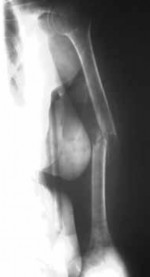

Figures 6a and 6b are the radiographs of a thin 23-year-old man who sustained a closed injury to his left arm in a fall. He has no other injuries and his neurologic examination is normal. What is the most appropriate treatment?